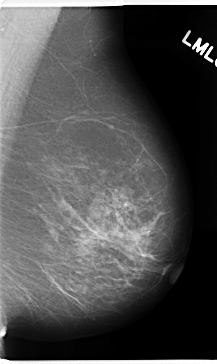

C_0172_1.LEFT_CC

LEFT_CC LINES 4760 PIXELS_PER_LINE 2616 BITS_PER_PIXEL 12 RESOLUTION 50 NON_OVERLAY